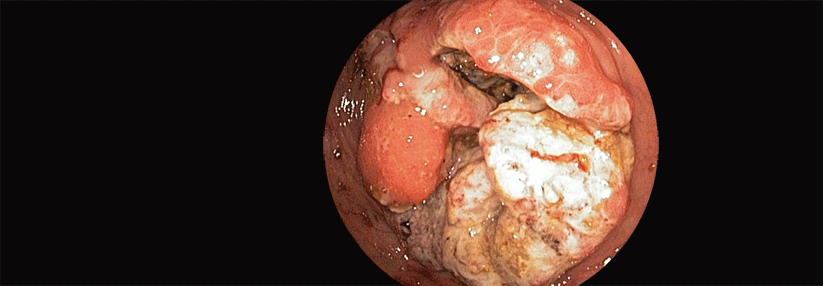

Aktuell stellen Somatostatinanaloga (SSA) einen Standard der Erstlinientherapie bei nicht-resektablen oder metastasierten GEP-NET vom Grad 1–2 dar, die Somatostatinrezeptor-positiv sind. In der STARTER-NET-Studie verglichen Forschende die Kombination des SSA Lanreotid mit Everolimus mit einer Everolimus-Monotherapie bei Patient:innen mit ungünstiger Prognose.

Bislang gibt es bei GEP-NET wenig Evidenz für die Kombination von SSA mit zielgerichteten Wirkstoffen, erklärte Dr. Dr. Susumu Hijioka vom Klinikum des Nationalen Krebszentrums in Tokio.1 Wie er nun berichtete, führte in der Phase-3-Studie STARTER-NET die Kombination von Lanreotid mit Everolimus zu einem etwa verdoppelten progressionsfreien Überleben gegenüber der Everolimus-Monotherapie.

In die Studie waren Personen mit nicht-funktionalem GEP-NET Grad 1/2 und nicht-resektabler oder rezidivierter Erkrankung mit einem Proliferationsindex (Ki-67) von 5–20 % oder diffuser Lebermetastasierung eingeschlossen worden. Alle hatten zuvor noch keine Therapie für die metastasierte oder rezidivierte…